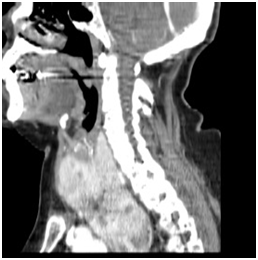

Figure 5 Goiter extending under aortic arch (sagittal view).